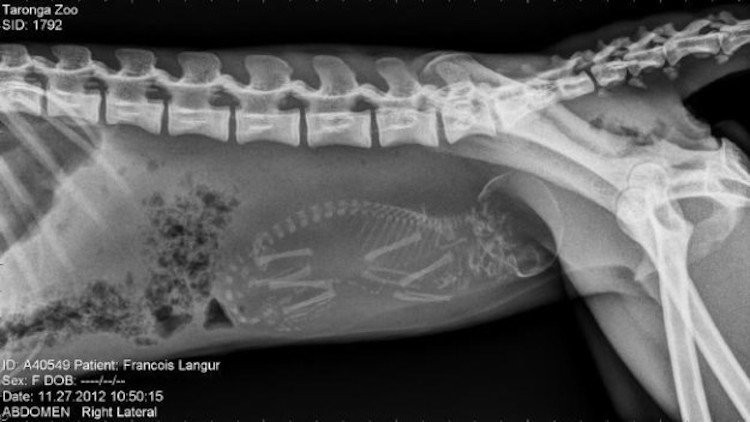

Le saviez-vous ? Le chat est une sous-espèce issue de la domestication du chat sauvage, qui vient lui-même de la famille des félidés. Animal de compagnie de l’homme, le chat compte une cinquantaine de races différentes.

Rareté de la nature, la chatte émet un nouvel ovule à chaque pénétration, ce qui fait que les chatons d’une même portée peuvent être de pères différents. La gestation dure 63 à 65 jours et une portée compte en moyenne quatre à cinq chatons. Dès leur naissance, la chatte lave immédiatement ses petits à coups de langue pour stimuler leur première inspiration. Ensuite, elle dévore le placenta, hautement nutritif, et coupe le cordon ombilical.

Le chaton naît aveugle (ses yeux sont clos) et sourd. Il n’ouvrira ses yeux qu’à l’âge de huit à douze jours, et ils seront de couleur bleue jusqu’au changement définitif (vers deux mois). Tous les petits naissent avec des rayures fantômes qui disparaissent à mesure de la pousse du poil. La chatte apprend à ses chatons à se laver, se nourrir, etc. L’émancipation se produit entre huit à douze semaines.